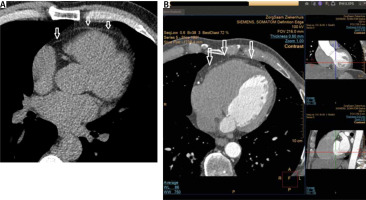

Cardiac CT

EAT volume can be assessed on non-contrast-enhanced CT and contrast-enhanced CTCA images [72–74]. Cardiac computed tomography (CCT) allows a clear depiction of the pericardium necessary for volumetric assessment of the EAT volume (Figure 2). Compared to echocardiography and CMR, CCT has the best spatial resolution [75] and visibility [9] of the pericardium, allowing reliable (manual) contouring of the visceral pericardial layer. Subsequently, the CT filter selects the voxels within the visceral pericardium with a CT attenuation coefficient attributed to adipose tissue (range –190 Hounsfield Units [HU] to –30 HU for non-contrast-enhanced CCT) [9, 75]. The total EAT volume is determined by summing all axial slices portraying EAT (Figure 3). EAT volumes can be assessed semi-automatically or by automated algorithms (quantifying both EAT volume and attenuation) [76–79]. Volumetric quantification of EAT by cardiac CT is highly reproducible [78].

FIGURE 2

Example of a non-contrast enhanced (panel a) and a contrast enhanced cardiac CT image (panel B). Note the good visibility of the pericardium (arrows) allowing a clear delineation of the epicardial fat (EAT) and adipocyte tissue outside the visceral epicardium